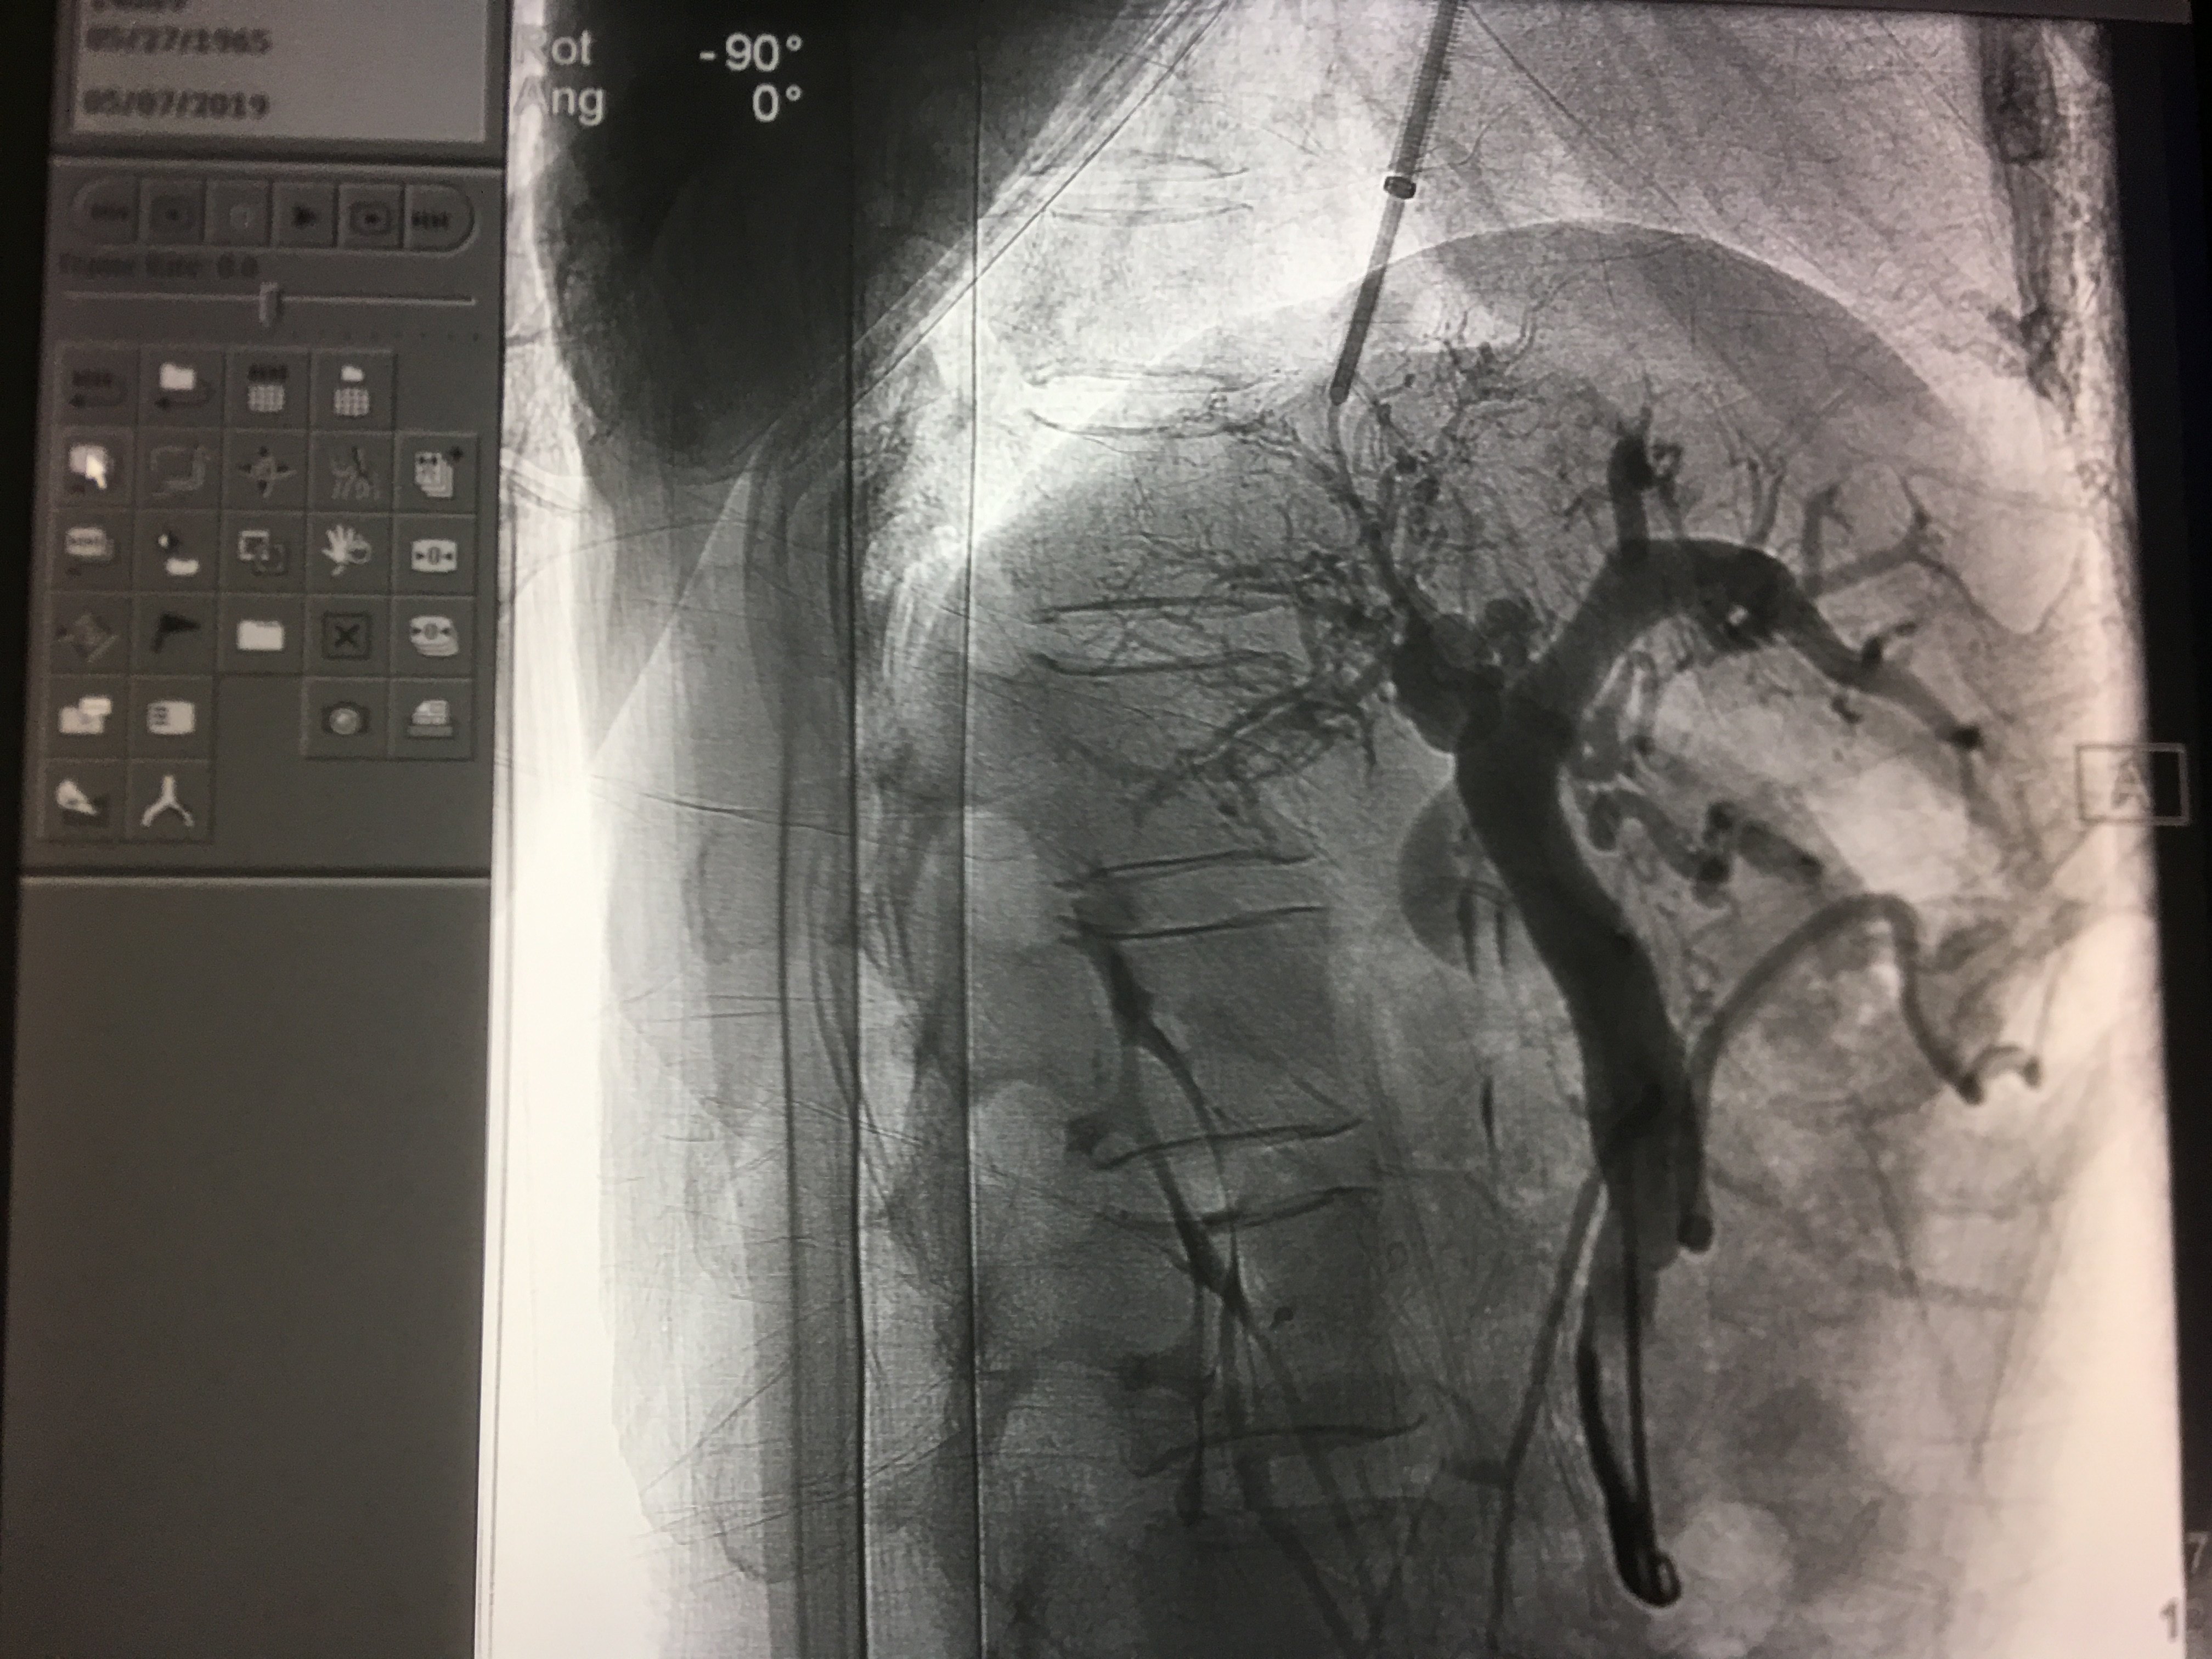

球囊扩张

支架置入后再次造影并测压,压力下降明显。